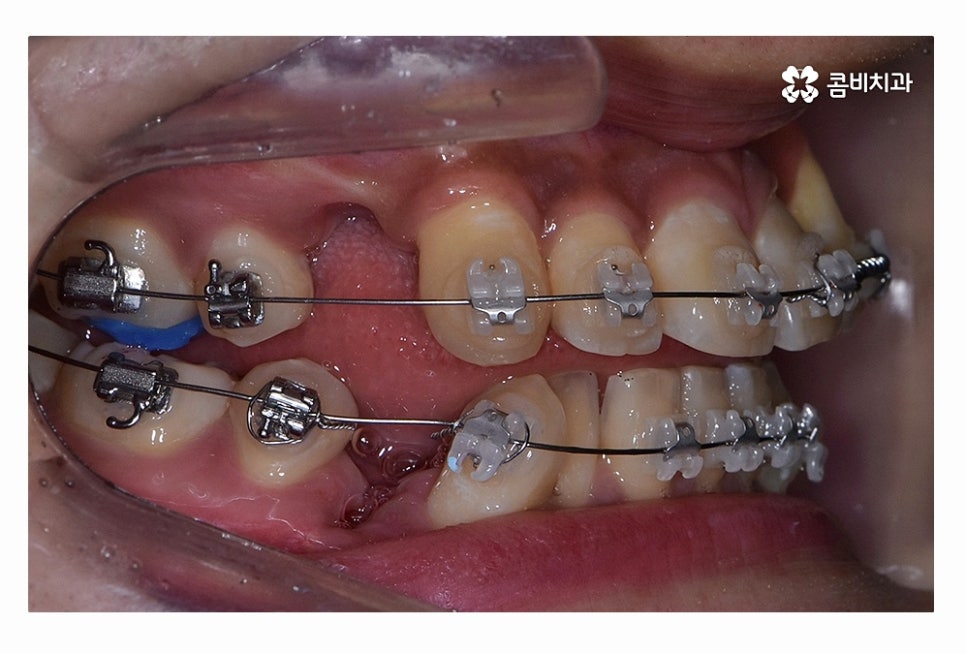

오늘 보시는 환자분의 사례처럼 덧니가 치아끼리 겹쳐 있는 경우에

치아의 이동 공간 확보를 위해서 덧니 발치 필요한 사례였으며

교합과 치아교정 후 얼굴 변화를 고려할 때도 치아교정 과정에서

발치가 필요한 사례였다고 볼 수 있어요.

치아교정 과정에서 덧니 발치 필요한 경우에는 덧니 자체를

발치한다고 생각하시는 분들도 계신데

꼭 그렇지는 않으며 앞서 설명드린 것처럼

치아의 이동 공간 확보와 교합을 고려하여 발치가 이뤄지고 있어요

일반적으로는 송곳니 옆의 작은 어금니를 발치하는

경우가 대부분이며 손상이 심한 치아가 있는 경우에는

손상도가 심한 치아를 발치하는 경우도 있어요